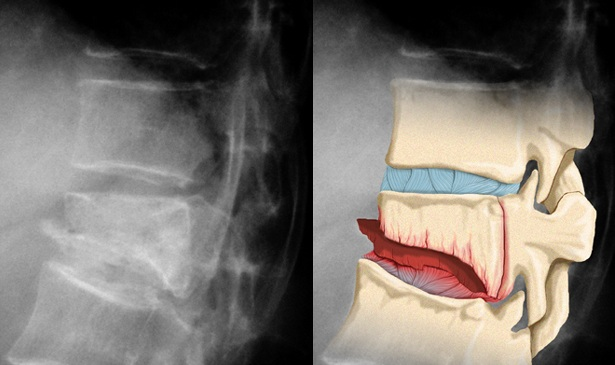

Рентгенологічне дослідження при травмах хребців

Для того, щоб компресійний перелом трьох хребців був підтверджений необхідно, щоб фахівець призначив рентгенографію хребта (це діагностичне дослідження є обов’язковою процедурою). Якщо отримані рентгенологічні знімки виявляються недостатньо інформативними можна скористатися комп’ютерної та магнітно-резонансної томографиями.

Механізм пошкодження хребетних фрагментів